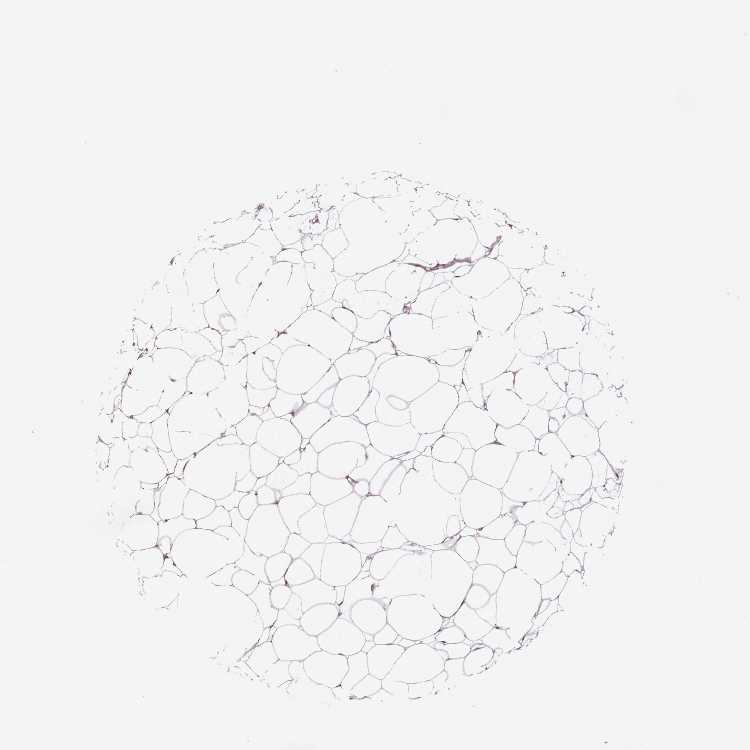

TISSUE PRIMARY DATA SOFT TISSUE Show tissue menu

SOFT TISSUE - Expression summary

SOFT TISSUE 1 - Antibody stainingi

Antibody staining in the annotated cell types in the current human tissue is reported as not detected, low, medium, or high, based on conventional immunohistochemistry profiling in selected tissues. This score is based on the combination of the staining intensity and fraction of stained cells.

Each image is clickable and will lead to virtual microscopy that enables deeper exploration of all samples and also displays staining intensity scores, fraction scores and subcellular localization as well as patient and tissue information for each sample.

Antibody HPA000262Antibody HPA006503

Fibroblasts LowNot detected

Peripheral nerve LowNot detected